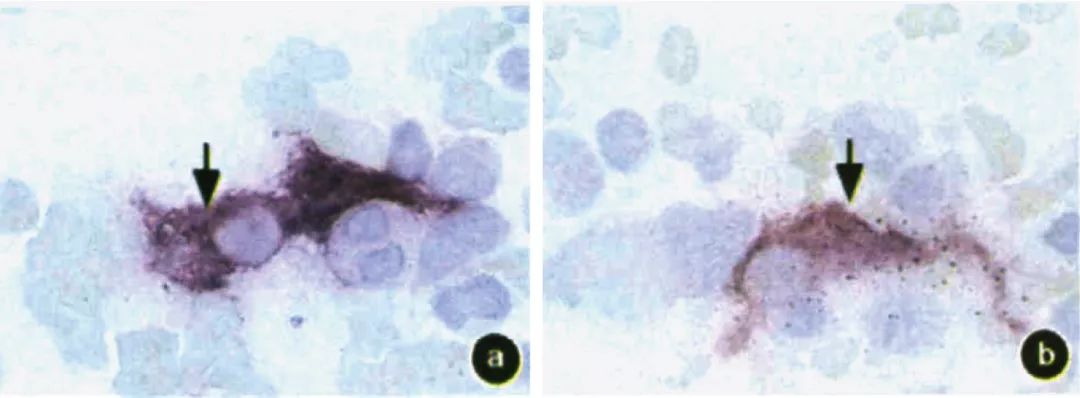

◆染色效果

图a~d: 骨髓涂片

a~d图箭头所示为骨髓基质细胞胞质染为紫红色,胞核不着色,而其他细胞均无此染色特征(固紫B盐染色x1000)